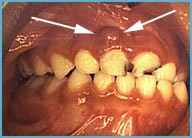

حالات قبل وبعد

معلومات طبية